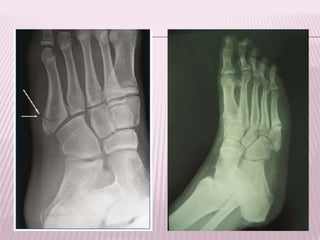

FRACTURA-LUXACIÓN DE LISFRANC

 Se produce por torción en el antepie fijo.

 Esta fractura corresponde a la linea articular

tarso-metatarsiana (por un lado la base de

los 5 metatarsianos y por otro las cuñas y los

cuboides).

 Clasificación Hardcastle:

 I. Homolateral

 Aislada

 Divergente

 El hallazgo mas importante en las

radiografias es la avulsión del 2 MTT